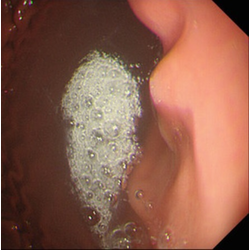

瀑 ばく 状胃の内視鏡検査 : 宇野コラム Uno column。

カスケード・ストマック 瀑状胃のぼこの庵。